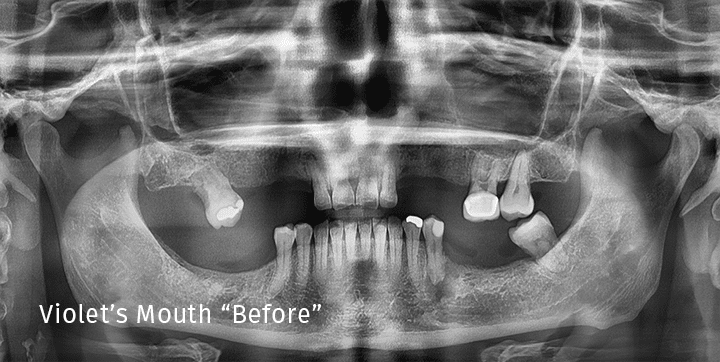

Patient teeth before full-mouth dental implant procedure Before

Patient smile after full-mouth dental implant transformation After